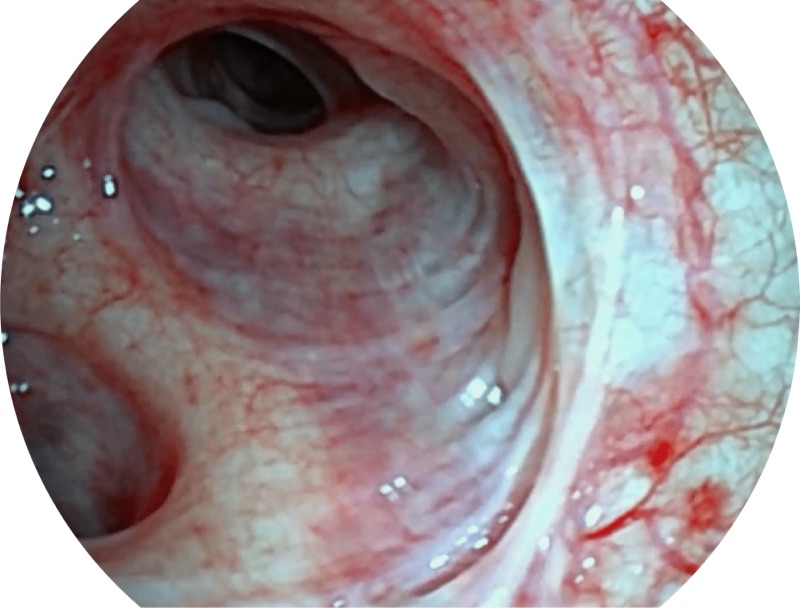

白光

帮助医生更加清晰地观察气管表面病灶